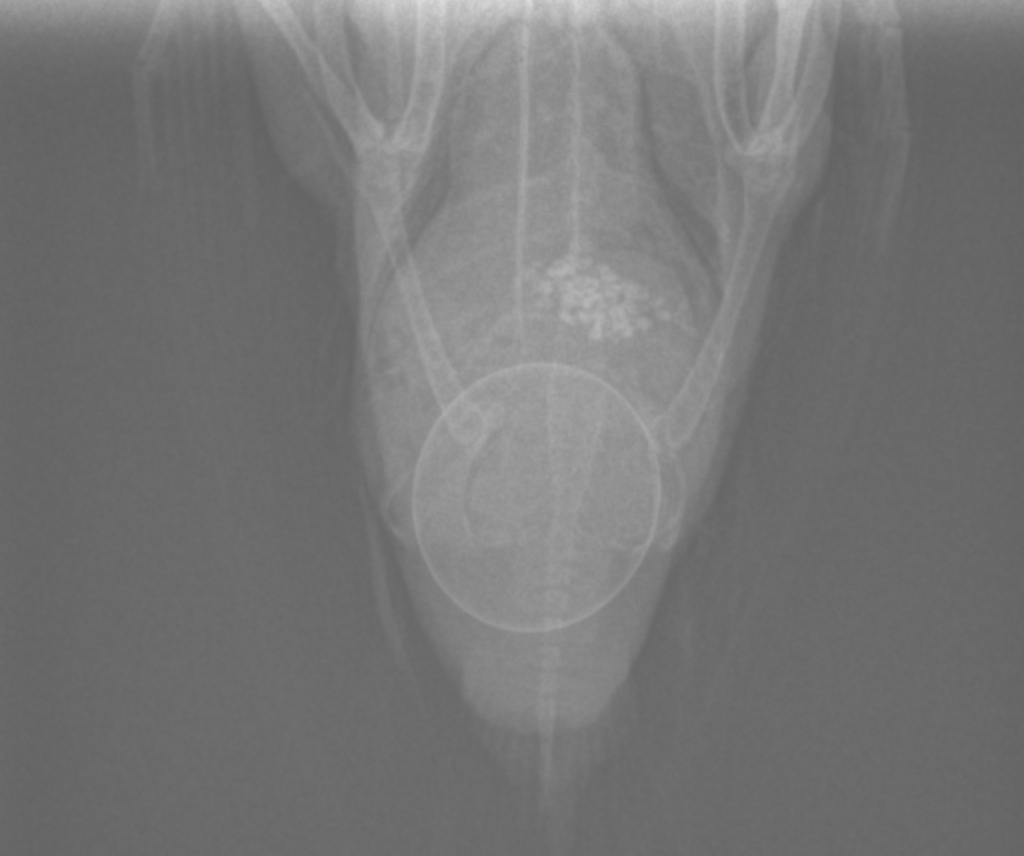

レントゲン検査をしてみると・・・

お腹の中に卵がありました。

- レントゲン検査:卵が詰まっている場所や大きさ、位置を正確に把握するためにレントゲンを撮ることが多いです。